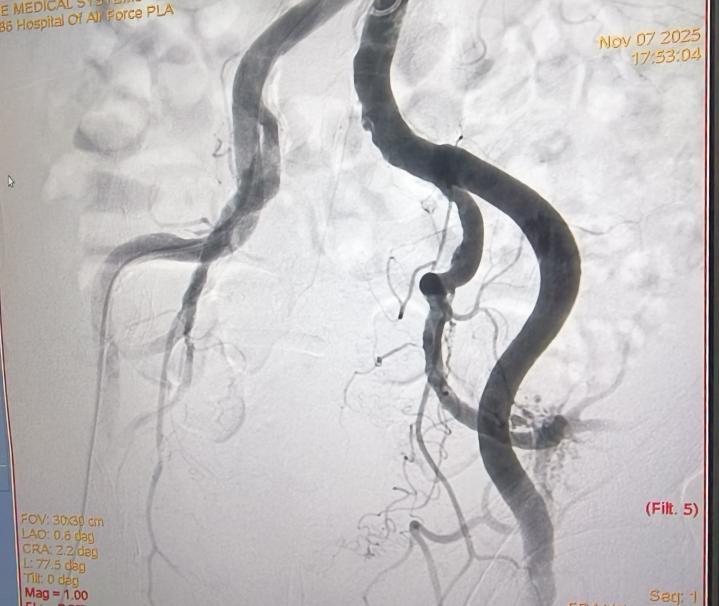

术前

11月7日下午,手术正式进行,全程在患者清醒状态下完成,痛苦小,术后仅需对穿刺点进行加压包扎,恢复迅速。术后第二天,李老先生即可下床活动,身体恢复良好,目前已康复出院。